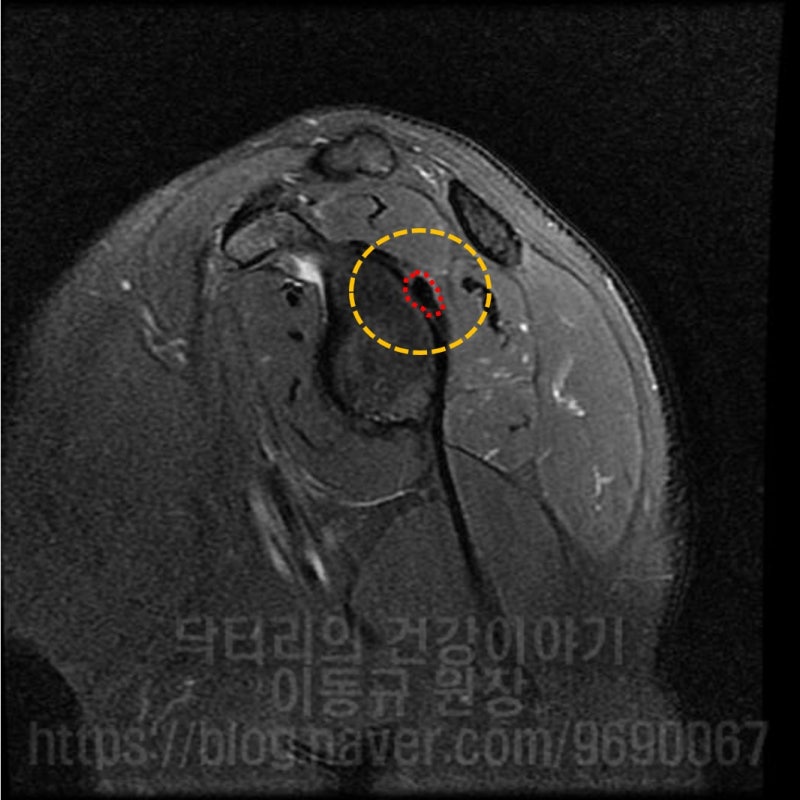

석회성 건염은 매우 통증이 심한 질환입니다. 대부분 회전근개 내에 발생되는 경우가 많습니다. 힘줄에 발생하게 되면 해당 힘줄을 움직일때 마다 극심한 통증을 유발하게 됩니다. 그런데 이러한 석회성 건염이 힘줄이 아닌 다른 곳에 발생된다면 어떨까요? 이번 케이스는 43세 여자 환자 분으로 평상시 피트니스 모델 및 대회를 나갈 정도로 운동을 활발히 하시는 분입니다. 2년전부터 어깨 통증이 발생되고 어깨 후방, 어깨 죽지로 통증이 심하게 있었던 분입니다. 마치 증상이 목 디스크로 인한 연관통 처럼 보이기도 하고 흉곽터널증후군 처럼 보이기도 합니다. 환자는 타 병원에서 목, 어깨 MRI 까지 촬영을 했지만 특별한 진단을 받지 못하고 경추부 문제 정도로 보인다는 이야기를 듣고 주사치료 및 도수치료만 받아오셨던 분이었습니다. 하지만 증상의 호전이 보이지 않고 점점더 통증이 심해지고 근력이 약해져서 저한테 내원하셨던 분이었습니다. 우선 이학적 검사를 해 보았습니다. 특별히 이학적 검사상 특이 소견을 보이지는 않았으나 biceps load test, O'brien test, E/R test 양성 소견을 보였습니다. 즉, 관절와순 병변이 의심되는 소견이었습니다. 가지고 온 영상 자료를 살펴 보겠습니다.

경추부 X-ray 와 MRI 도 확인했으나 특이소견은 없었습니다. 즉 이 환자분은 조금 특이한 위치에 석회가 있으면서 어깨 통증을 유발된 환자고 위치적으로 상견갑신경과 비슷한 위치에서 염증을 일으키다 보니 경추부 문제로 오진되어 치료를 제대로 받지 못했던 경우로 판단됩니다. 위치적으로 뉴핌스치료(석회분쇄흡입술)을 할 수 없는 위치이며 상부관절와순 손상에 대한 치료를 동시에 하기 위해 수술적 치료를 결정하였습니다.